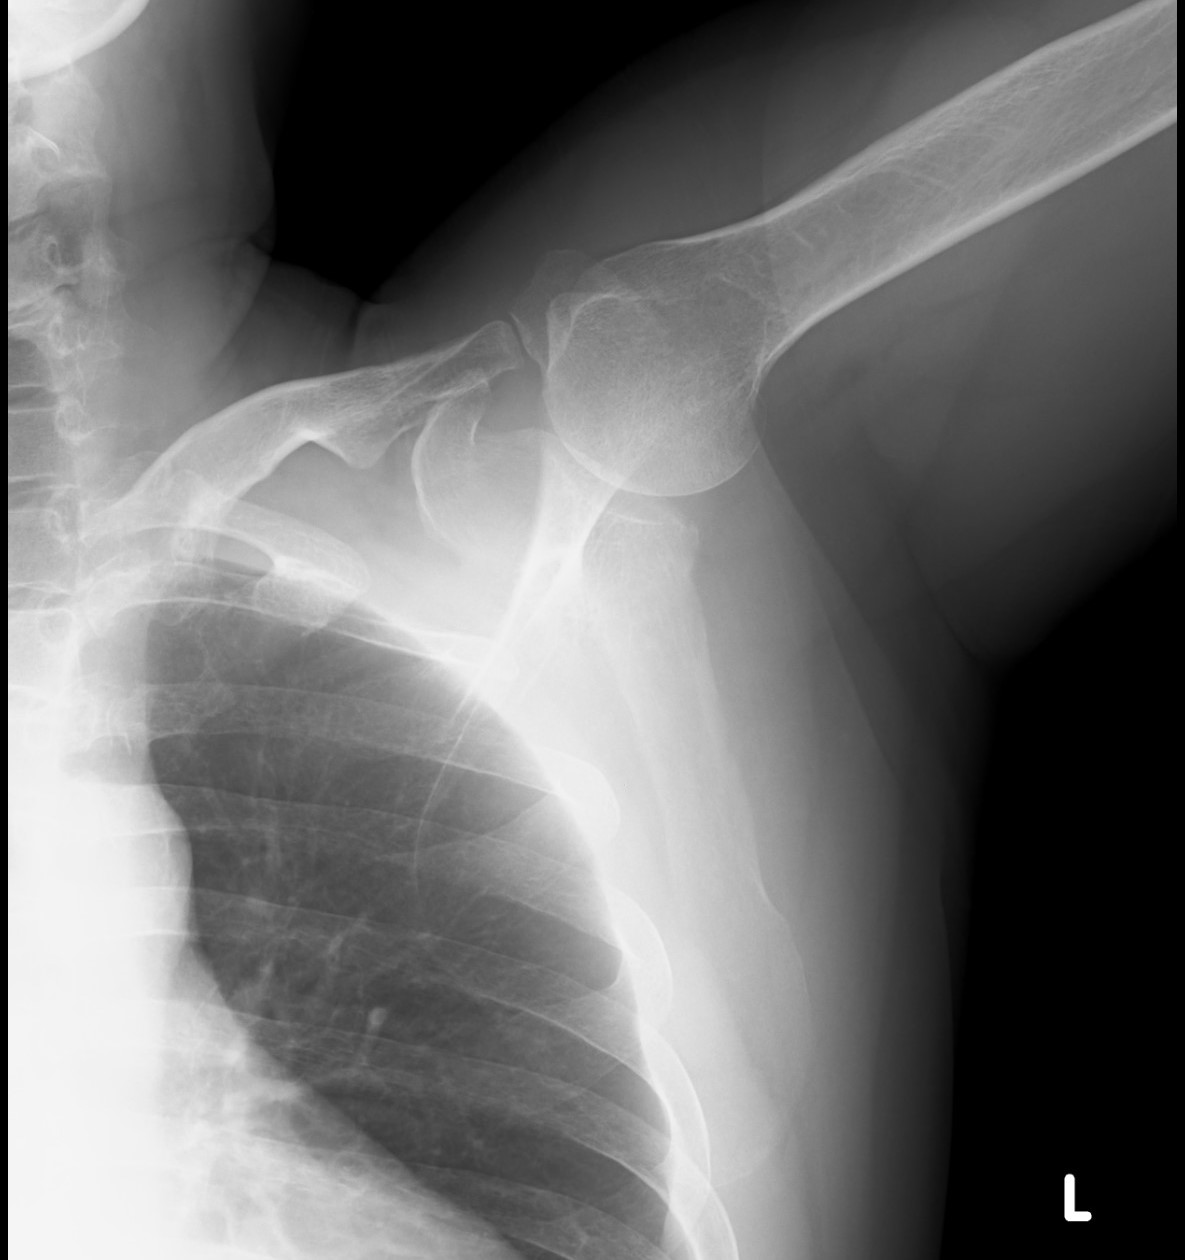

主な対象となる症状には、肩の痛み、動かしにくさ(可動域制限)、肩こりの悪化、腕が上がらないといったものがあります。具体的な疾患としては、五十肩(肩関節周囲炎)、腱板断裂、インピンジメント症候群、石灰沈着性腱炎、脱臼やスポーツ障害などが挙げられます。

診療では、問診や身体診察に加え、レントゲンやMRI、超音波検査などの画像検査を用いて正確な診断を行います。そのうえで、リハビリテーション、薬物療法、注射治療(ヒアルロン酸やステロイドなど)、必要に応じて手術療法まで、患者さん一人ひとりの状態に合わせた治療方針を提案します。